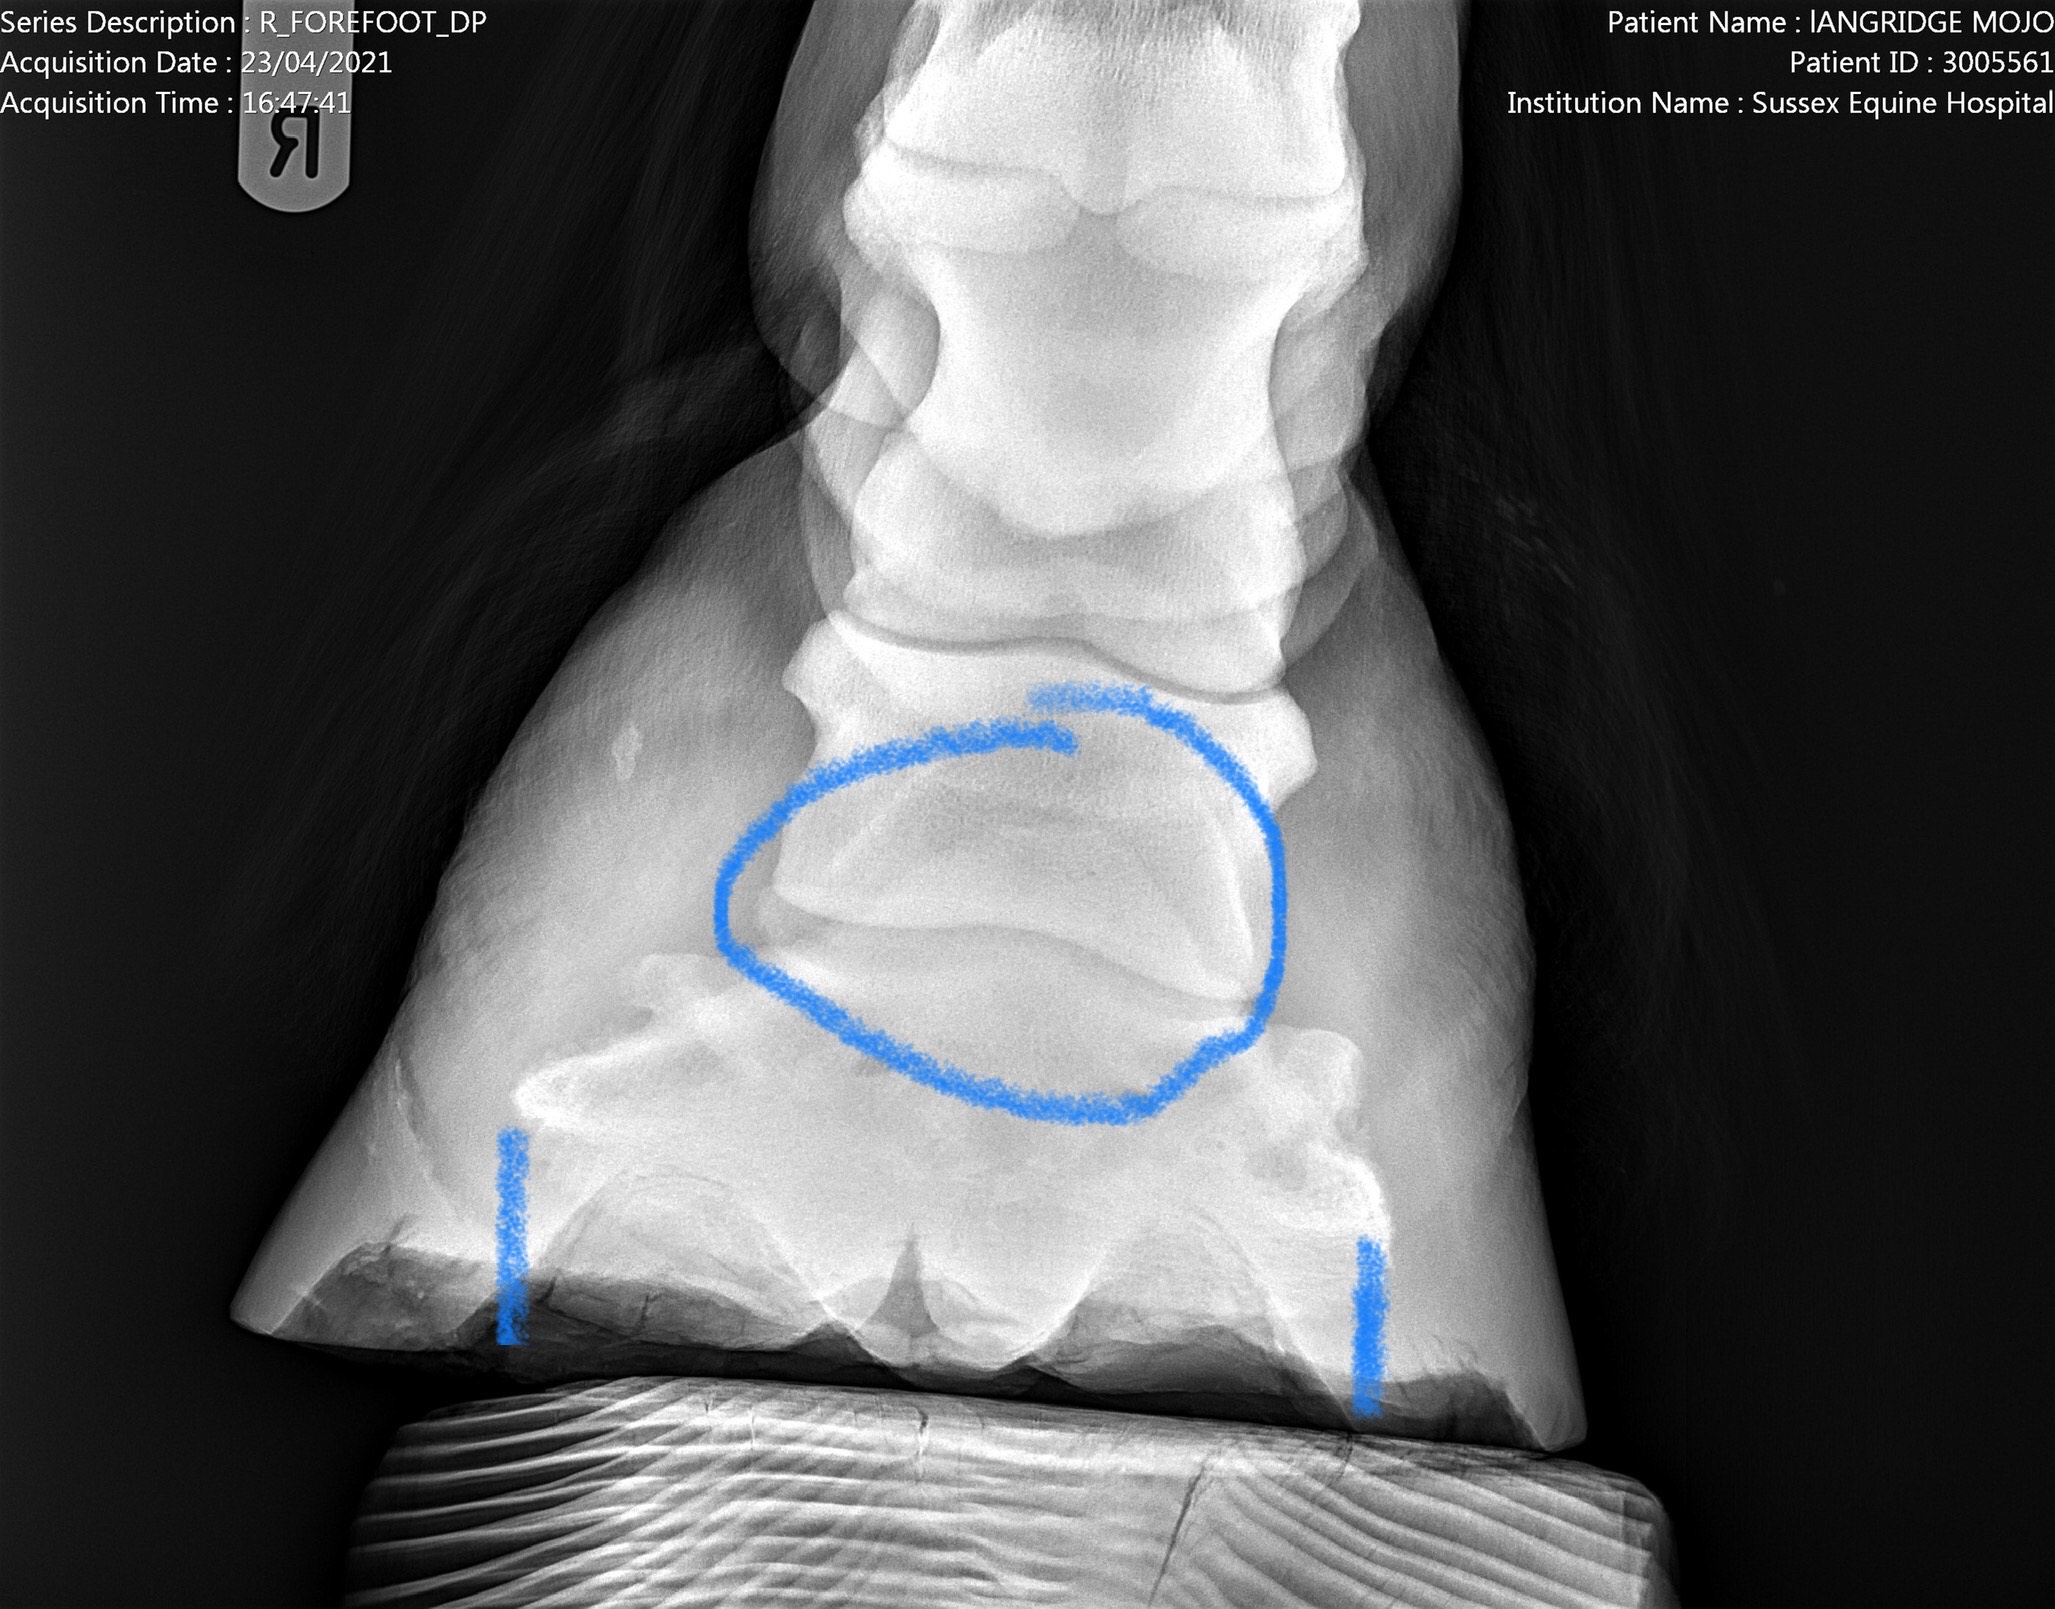

23rd April 2021 x-rays taken of front feet and both hocks.

Mojo was very good, he put his feet on the blocks and stood still for the front feet and one hock. He was very protective of his right hock but it was done with no sedation – just lots of treats.

Lots of changes in both fetlocks and multiple small avulsion fragments of the sesamoids. Hocks didn’t seem too bad so the plan is to turn out – he doesn’t run about anyway, and keep on bute for now.